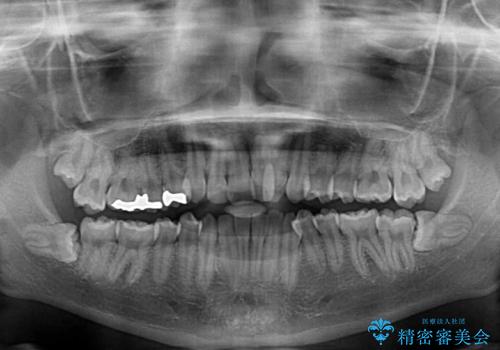

上顎骨の横幅が狭く、奥歯は上顎よりも下顎が外側にある咬合状態でした。

歯列矯正では基本的に骨格を改善することはできませんが、急速拡大装置(MARPE)を使用することで上顎骨を側方に拡大させることができ、咬合状態を大きく改善することができます。

事前に急速拡大装置で側方拡大を行い、上下を目立たないワイヤー装置により歯列を整えていくこととしました。